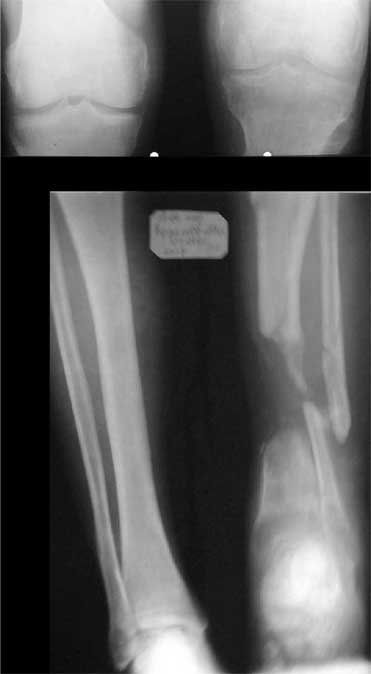

В приложении - моё наблюдение (возможно, уже представлял, тогда

извините).

Нога попала в пресс.

Ко мне больной попал черз 1,5-2 года после травмы и нескольких

операций с синегнойной инфекцией на всю голень. Меня пригласили на консультацию

насчет ампутации.

Лечил я его месяцев 8.

Малоберцовка полностью перестроилась, нога опороспособна.

При ходьбе на дальние расстояния пользуется тростью.

Осталась трофическая язва, периодически закрывается.

Клинические снимки где-то есть, но не очень качественные.

Один из вариантов.

С уважением Александр Артемьев